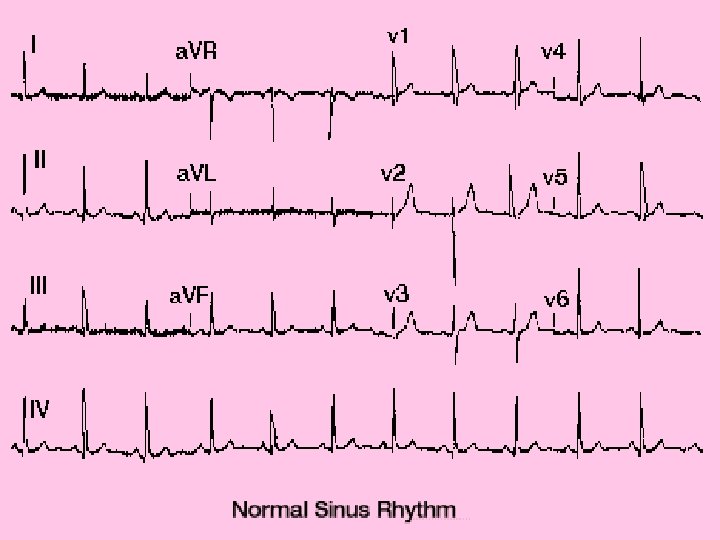

CONDUCTIVE PATHWAY • Electrical impulses starting in the heart cause contraction of the muscles.

Sinoatrial node (SA) • Group of nerves located in right atrium • Pacemaker • Sends electrical impulse that spreads over muscle of atria • Atrial muscles contract then push blood into ventricels. • After impulse goes through atria reaches the Atrioventricular (AV) node.

Atrioventricular (AV) node • • Group of nerve cells Located between the atria and ventricles Electrical impulse through septum Nerve fibers in septum called bundle of HIS

Bundle of HIS • Nerve fibers in septum • Right and left bundle branches

Right and left bundle branches • Carry impulse down through ventricles • Subdivide into a network of nerve fibers in ventricle called purkinje fibers.

Purkinje fibers • Final conduction pathway • Spread to all muscle tissue in the ventricles • Ventricles contract

Conduction • Occurs approximately every 0. 8 seconds. • Electrical impulse can be recorded on an EKG • Used to detect abnormal activity or disease.